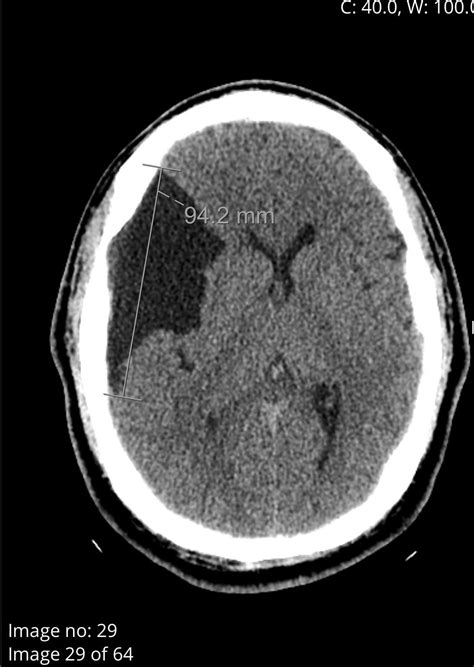

Symptoms often develop gradually as the cyst grows and exerts pressure on surrounding brain tissue. In some cases, symptoms can be sudden and severe, particularly if the cyst ruptures or causes a blockage in the flow of cerebrospinal fluid (CSF).

Diagnosing a cyst in brain typically involves a combination of medical history, physical examination, and imaging tests. The most common diagnostic tools include:

• Magnetic Resonance Imaging (MRI)

• Computed Tomography (CT) scan

MRI is often the preferred method for diagnosing brain cysts because it provides detailed images of the brain and can help differentiate between different types of cysts. CT scans are also useful and can be particularly helpful in emergency situations where quick imaging is needed.